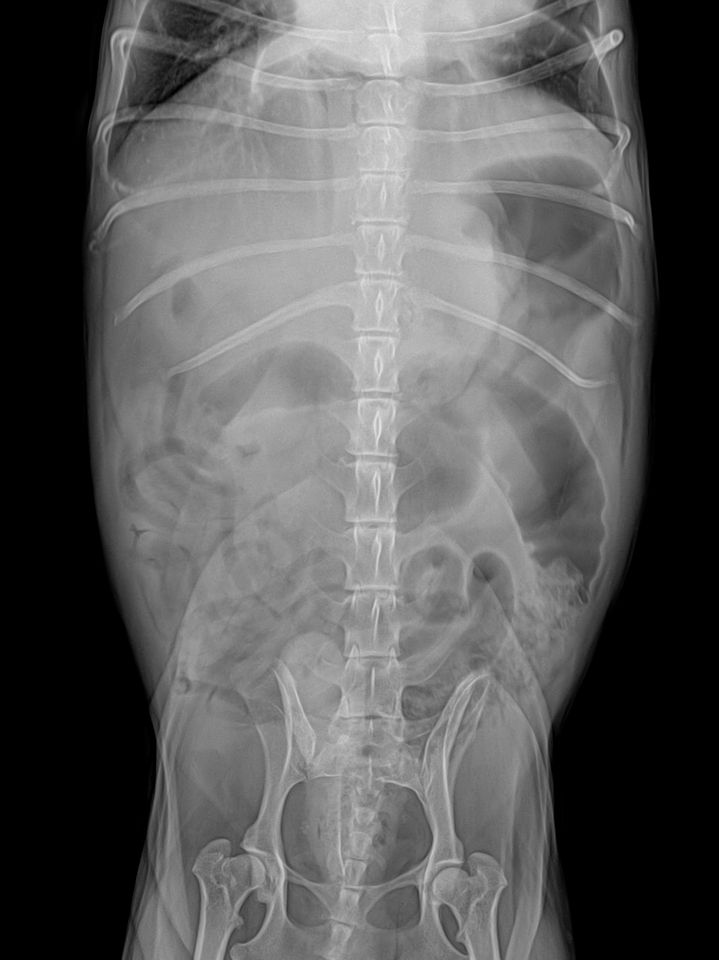

심장도 키기가 매우 크고, 좌심방 돌출이 있으며, 경미하지만 폐수종이 발생한 상태면서, 흉수도 보입니다.

또한 간의 크기가 큰데, 종괴 양상이 보여 간암 가능성이 매우 높아 보이니 복부 초음파 검사와 심장 초음파 검사 모두 필요합니다.